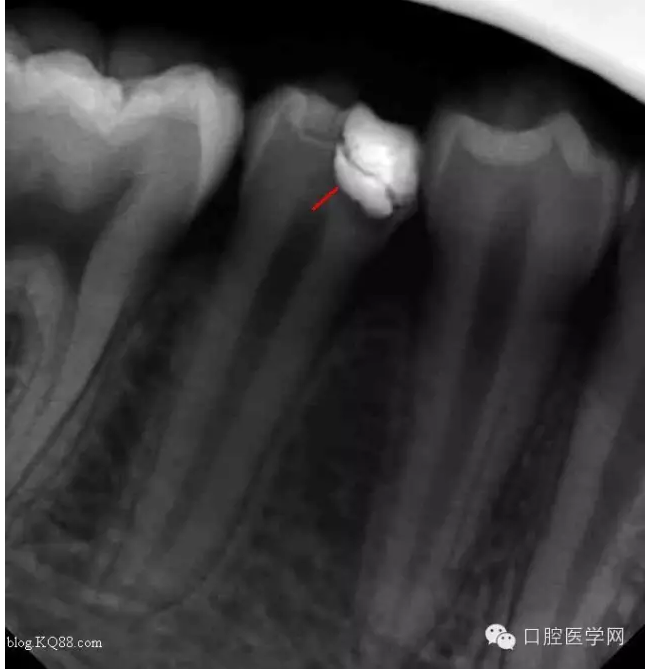

病人是我的助手,牙齒酸痛一周。吃冷熱時加重。無自發(fā)痛。先看看牙片

根據(jù)主訴:一過性冷熱痛無自發(fā)痛,X線:根尖無明顯改變應(yīng)診斷為深齲。小伙子平時愛吃冷飲最近冷飲是不敢吃了。

去腐,備洞。發(fā)現(xiàn)已經(jīng)露髓。根據(jù)年輕恒牙保存活髓治療原則。選擇直接蓋髓術(shù)?;颊呤俏业闹种辣4婊钏璧闹匾裕灾皇亲隽撕唵蔚臏贤?。如果其他病人遇到這種情況術(shù)前溝通很重要。首先灌輸保髓的重要性,告知術(shù)后反應(yīng),以避免不必要的麻煩

一月后復(fù)查:高聳的髓角變鈍,形成約0.5mm修復(fù)性牙本質(zhì)?;佳罒o癥狀。牙髓活力測試同對照牙。

兩月后復(fù)查:高聳的髓角變的更鈍。遠中髓壁形成較厚的修復(fù)性牙本質(zhì)。溫度測試同對照牙。

三個月后復(fù)查:高聳的髓角消失。形成約1mm的修復(fù)性牙本質(zhì)?;佳罒o癥狀,溫度測試同對照牙。此時修復(fù)性牙本質(zhì)的形成已趨于穩(wěn)定。每次復(fù)查的溫度測試是判斷牙髓活力,有時雖然沒有臨床癥狀,但牙髓受到慢性刺激會無痛性漸進性壞死。導(dǎo)致保存活髓失敗。